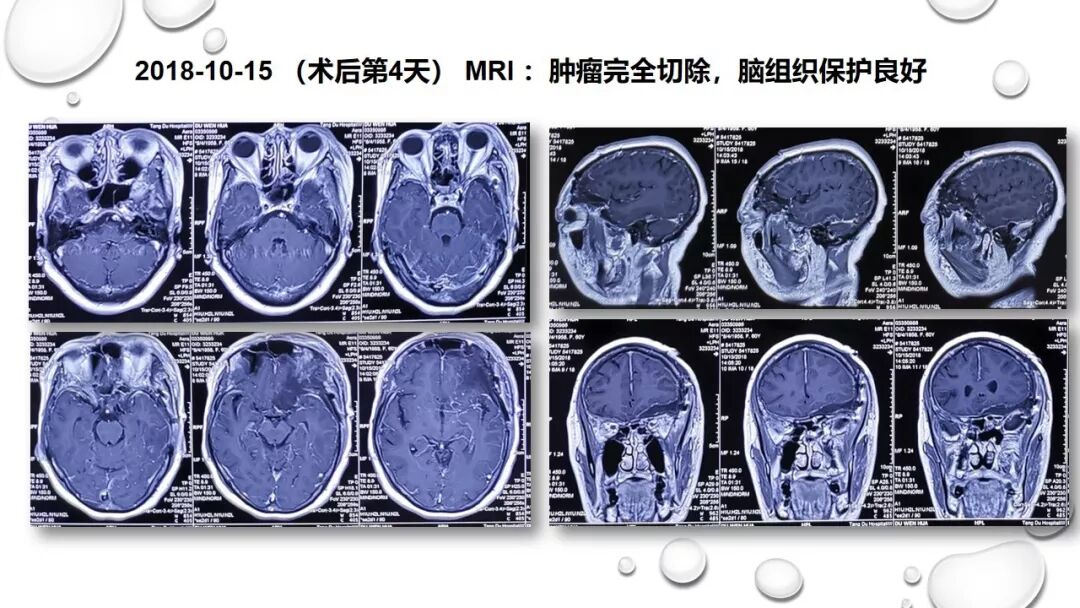

前床突磨除